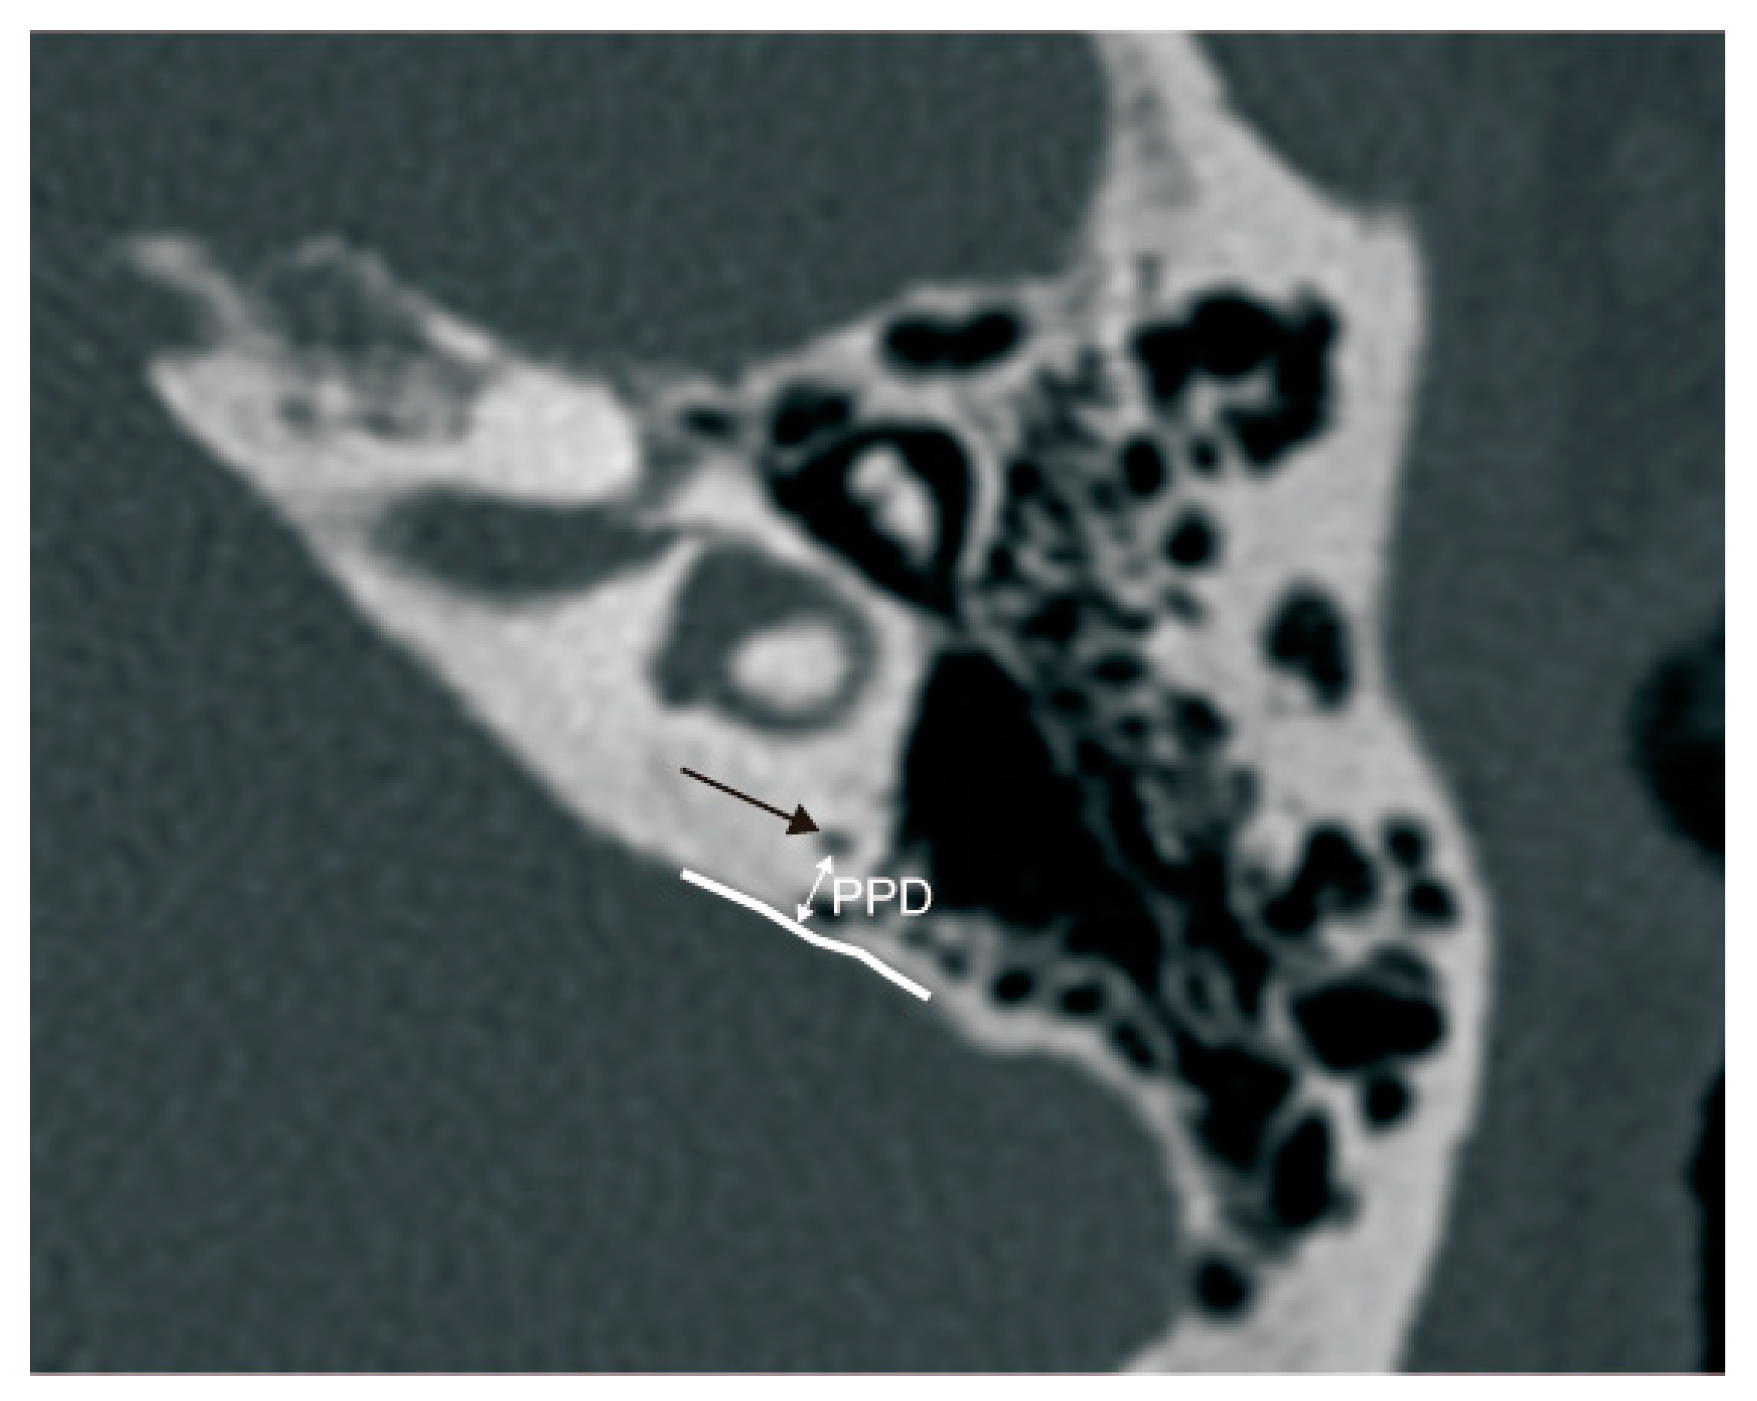

3.2.2. The Relationship between ATVA and PPD

4.2.2. The Relationship between ATVA and PPD

2.2.2. Radiological Measurement